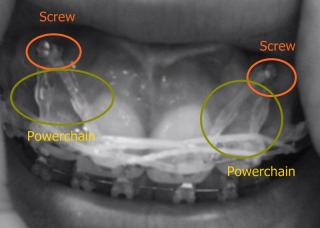

Dr removed the powerchain (powerchain is used to hook up the brackets to the screws). Powerchain has been removed. Screws are still there till date.

Hmmm... perhaps you can post a photo of it too. I'm curious all the powerchain and screw looks like

Yes, its quite complicated. I think we are in the same boat. Anyways, for those who are curious, click spoiler below for pictures.

» Click to show Spoiler - click again to hide... «

I had the pics in B/W cos i dun wanna gross you out... blush.gif